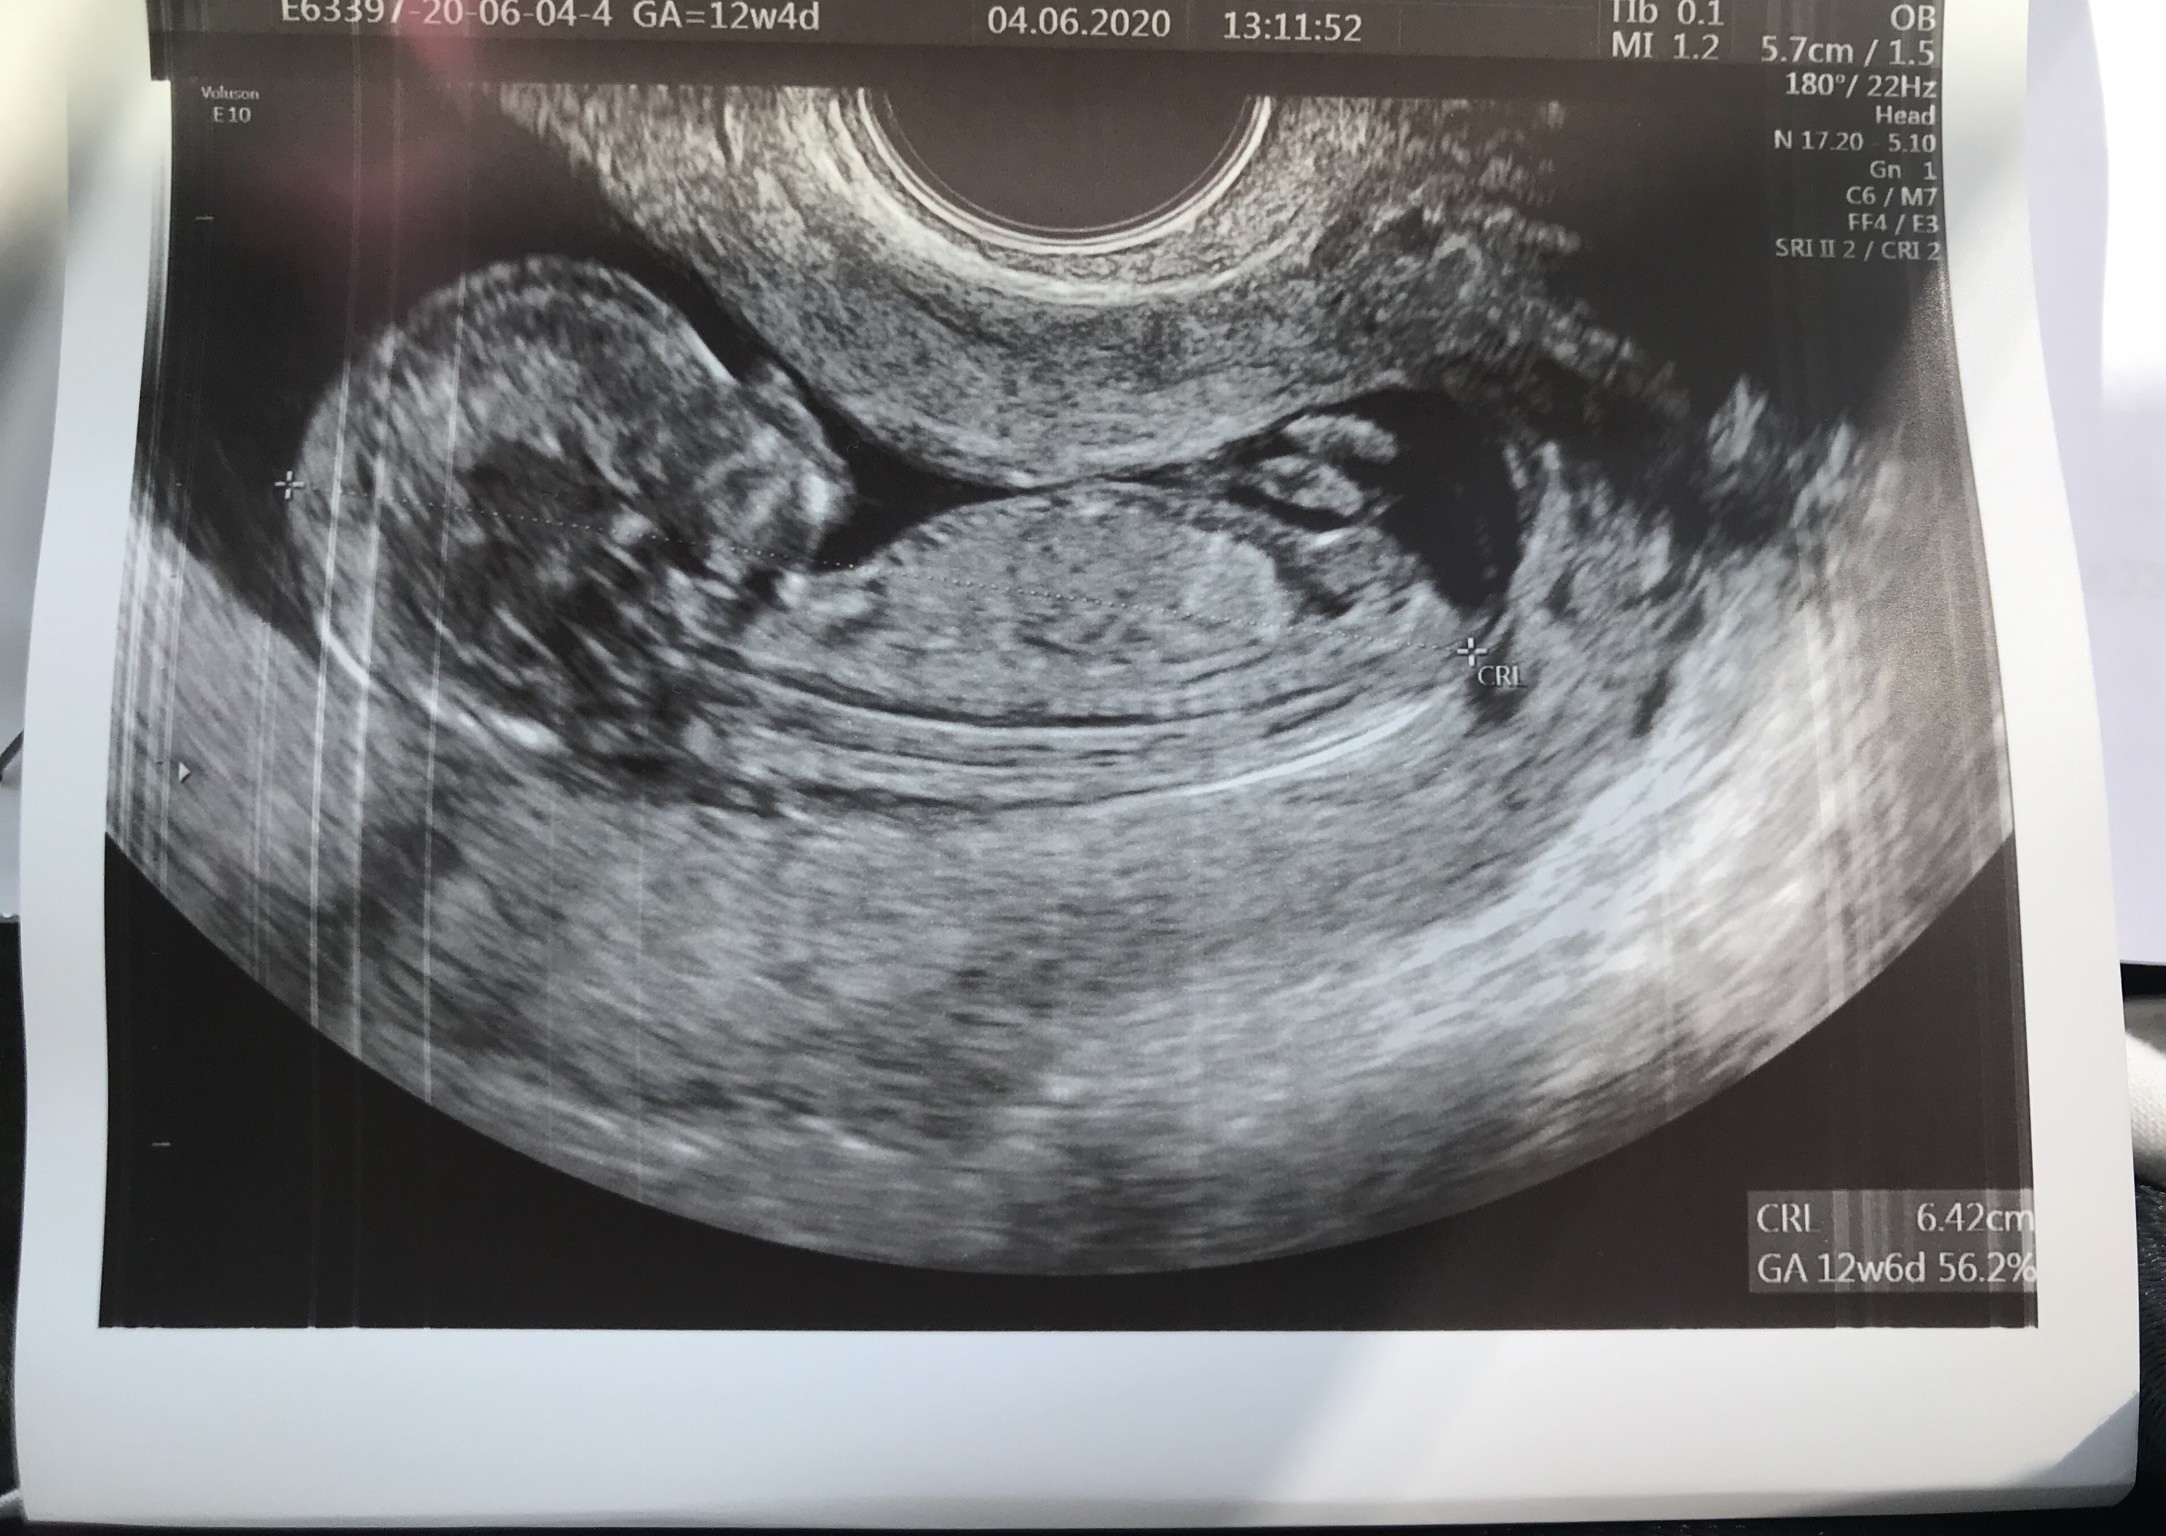

Ja już po wizycieBobo ma 9.3 cm

serducho słyszałam, bije 146 uderzeń/min. Jeszcze nie jest to pewne na 100% ale mojej córeczce (wg prenatalnych) chyba zaczynają rosnąć jajka między nogami